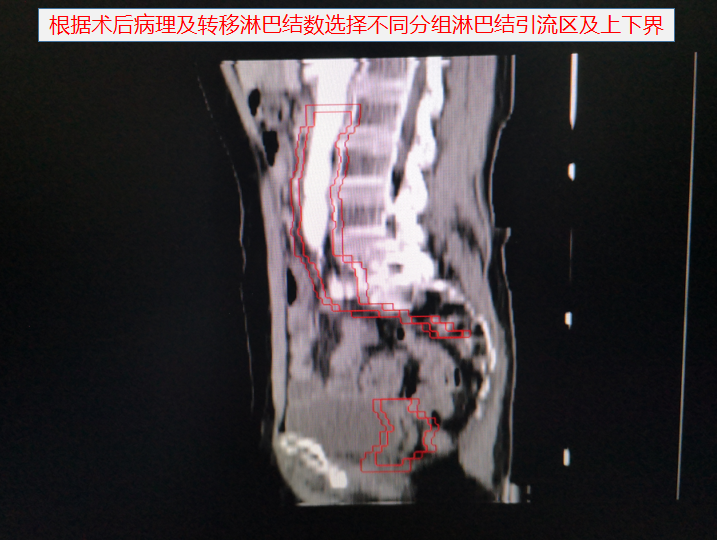

胃癌術後靶區勾畫示例: